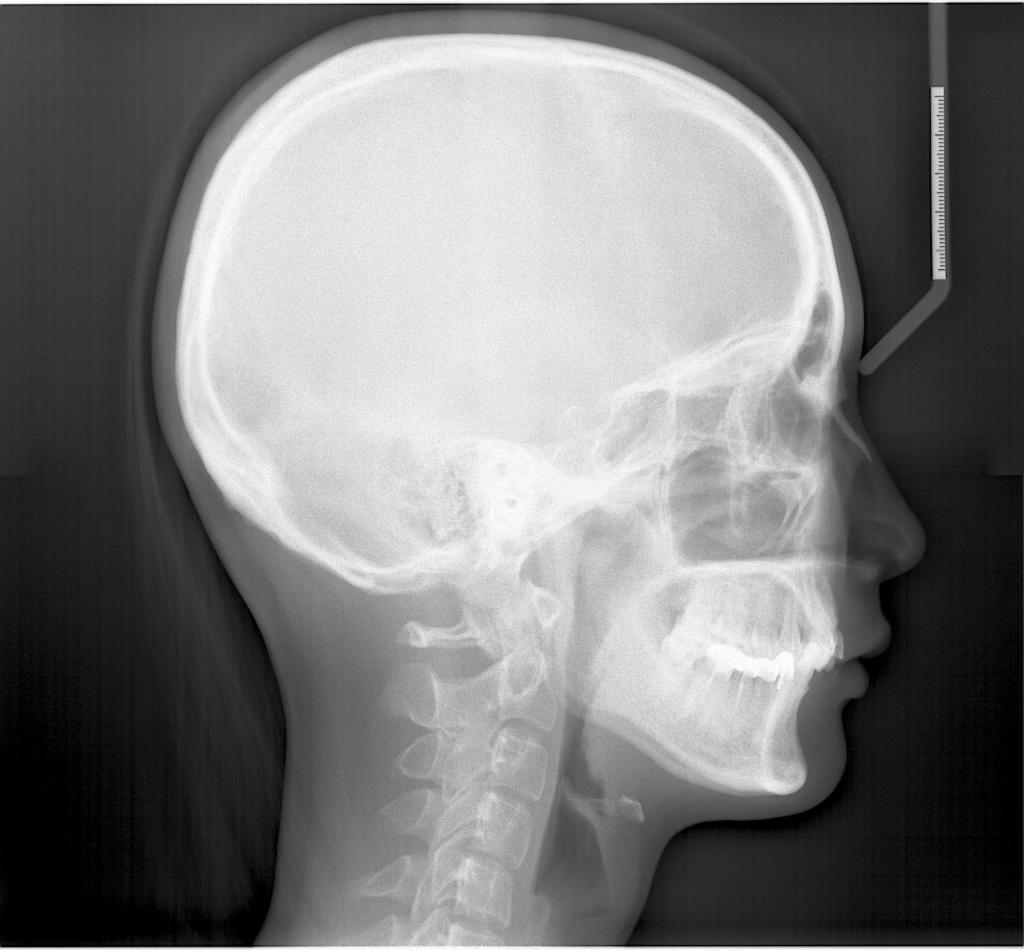

头影测量侧位/正位片